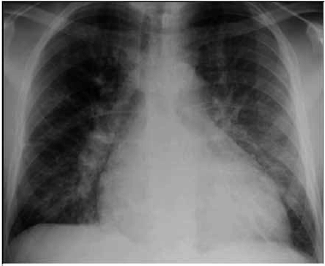

Paciente do sexo masculino, 57 anos de idade, acompanhado pela esposa, procurou serviço de urgência por dispneia aos pequenos esforços, edema de membros inferiores, diminuição do volume urinário, tosse seca associada a dispneia progressiva. Os sintomas se iniciaram há, aproximadamente, 6 meses, com dispneia seguida de edema. A dispneia, que era aos esforços moderados, rapidamente progrediu até estar presente no repouso. À ausculta pulmonar apresentou roncos e estertores em bases pulmonares. Ao raio X apresentou a radiografia a seguir:

(Arquivo pessoal, imagem usada com autorização)

Com base nas informações apresentadas no caso clínico e na imagem, qual conduta inicial mais adequada?

Ao exame físico, apresentou-se ansioso, agitado, dispneico, taquipneico, com frequência respiratória (FR) de 36 ipm, pressão arterial (PA) de 200/118 mmHg, frequência cardíaca (FC) de 104 bpm, temperatura (T) de 36,8 °C, saturação periférica de oxigênio (SpO2) de 88% com cateter nasal 3 L/min de oxigênio. Coletada gasometria arterial: pH: 7,16; PO2: 70; PCO2: 65; HCO3: 23; BE: –2. Considerando esses dados, o caso clínico e a imagem apresentados, assinale a alternativa correta quando ao provável diagnóstico.

Qual o provável diagnóstico de acordo com o caso clínico e com a imagem apresentados?